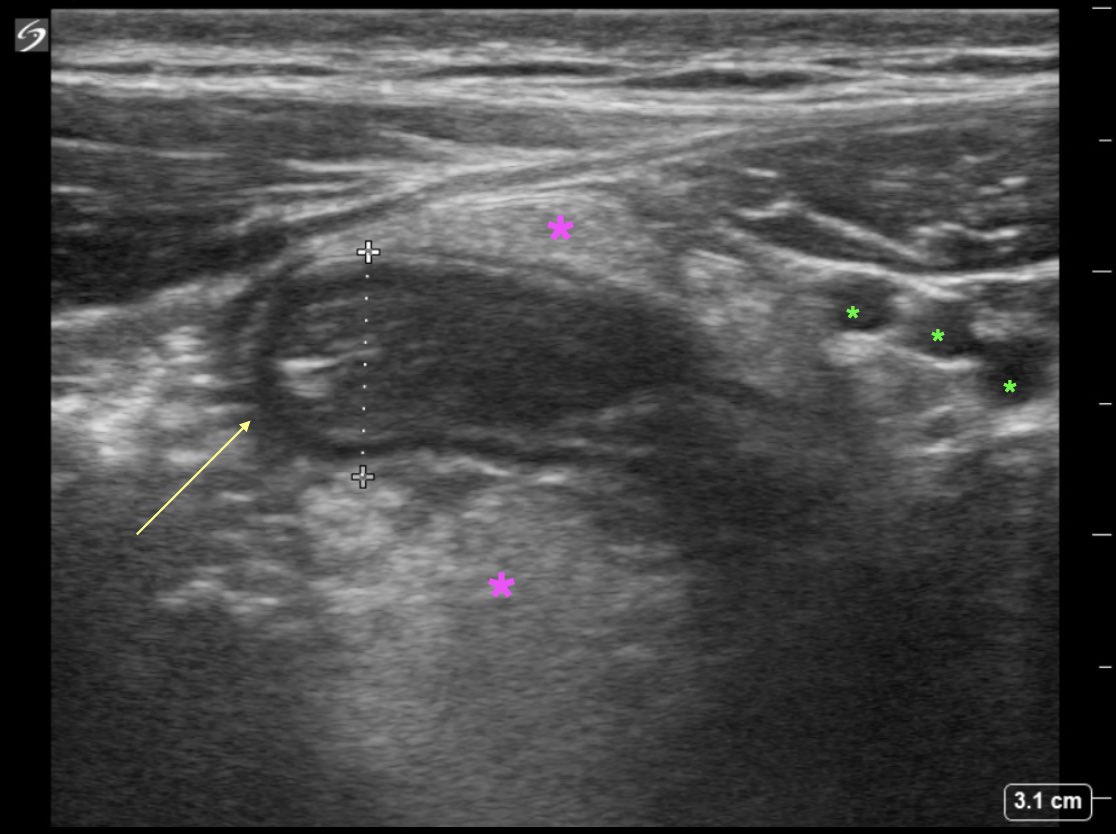

Students: What structure is represented by the yellow arrow (measuring 9mm)? Residents: What is represented by the pink stars? What structures are the green stars indicating? #raysofgray #POCUS #ultrasound #FOAMed #MedEd #emergencymedicine #medicalstudent #resident

EUSmkh's tweet image. Students: What structure is represented by the yellow arrow (measuring 9mm)?

Residents: What is represented by the pink stars? What structures are the green stars indicating?

RESOLUTION S: 9mm structure (yellow arrow)—>inflamed appendix (>6mm, non compressible, no peristalsis, blind ended) R: pink stars—>inflamed fat, green stars —>inferior epigastric vessels #raysofgray #POCUS #ultrasound #FOAMed #MedEd #emergencymedicine #medicalstudent #resident

EUSmkh's tweet image. RESOLUTION

S: 9mm structure (yellow arrow)—>inflamed appendix (>6mm, non compressible, no peristalsis, blind ended)

R: pink stars—>inflamed fat, green stars —>inferior epigastric vessels